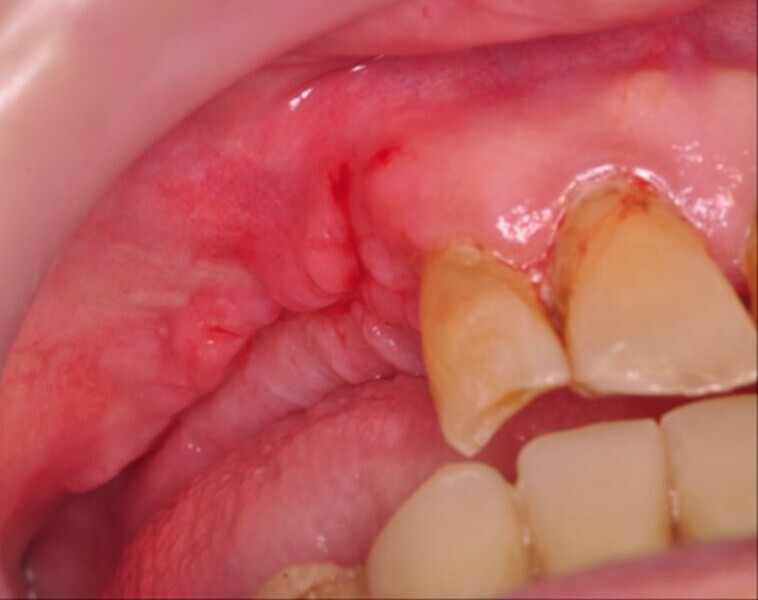

Osteonekroza występująca po zastosowaniu bisfosfonianów